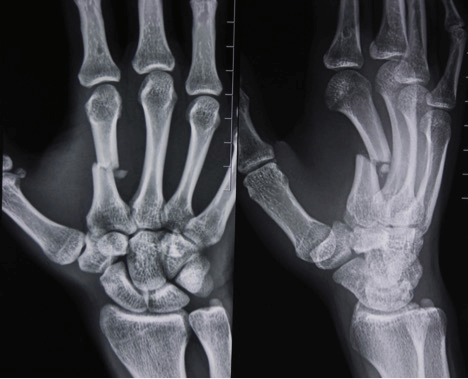

При подозрении на перелом кисти необходимо обратиться к травматологу. Первоначальный диагноз врач ставит на основе сбора анамнеза, анализа жалоб пациента и внешнего осмотра. Чтобы исключить вывихи или сильный ушиб, назначают рентген в двух или трех проекциях.

В некоторых случаях сразу сделать рентген не получается из-за сильного отека мягких тканей. В таких случаях обследование проводят через 8-10 дней. На это время поврежденную руку фиксируют жесткой гипсовой повязкой или полимерными бинтами.

• рентгенологическое обследование в стандартных двух проекциях на уровне запястья и кисти (переднезадней и боковой) - линии переломов могут быть поперечными, косыми, спиральными, продольными, краевыми с отрывом места прикрепления сухожилий, внутрисуставными и внесуставными.